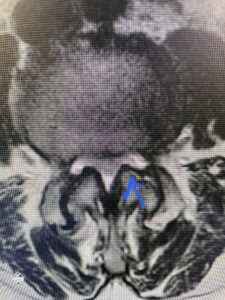

Another patient is a 62 year-old female with progressive low back pain and right leg pain and numbness that radiates to the top of her foot. She tried physical therapy and epidural injections. MRI demonstrated severe L3-4 stenosis and a grade 1 spondylolisthesis (Fig 4). There was L5-S1 and L4-5 disc collapse with modic end-plate changes. Biomechanically because of the significant degeneration of these disc spaces which stiffened the L4-S1 segment more stress was placed on the L3-4 segment, resulting in significant premature degeneration and compensatory stenosis and segmental instability. The MRI also showed pathologically, because of the slip, the L3 inferior processes were more anteriorly oriented and hence contributing to the majority of the lumbar canal compromise. Note the more sagittally-oriented facets in this case compared to the prior case (Fig 5). The patient underwent a decompressive laminectomy with attention of removing the inferior processes of L3 to fully decompress the canal. We also performed an L3-4 fusion with instrumentation (Fig 6). The patient had an uneventful postoperative course with improvement of leg pain. Of note with relief of the disabling leg pain patients are generally very happy. Patients can often manage their low back pain; it is the leg pain that they just can’t tolerate.

Fig 5 Axial T2-weighted lumbar MRI demonstrating significant L3 inferior facet contribution of severe stenosis (blue arrow)